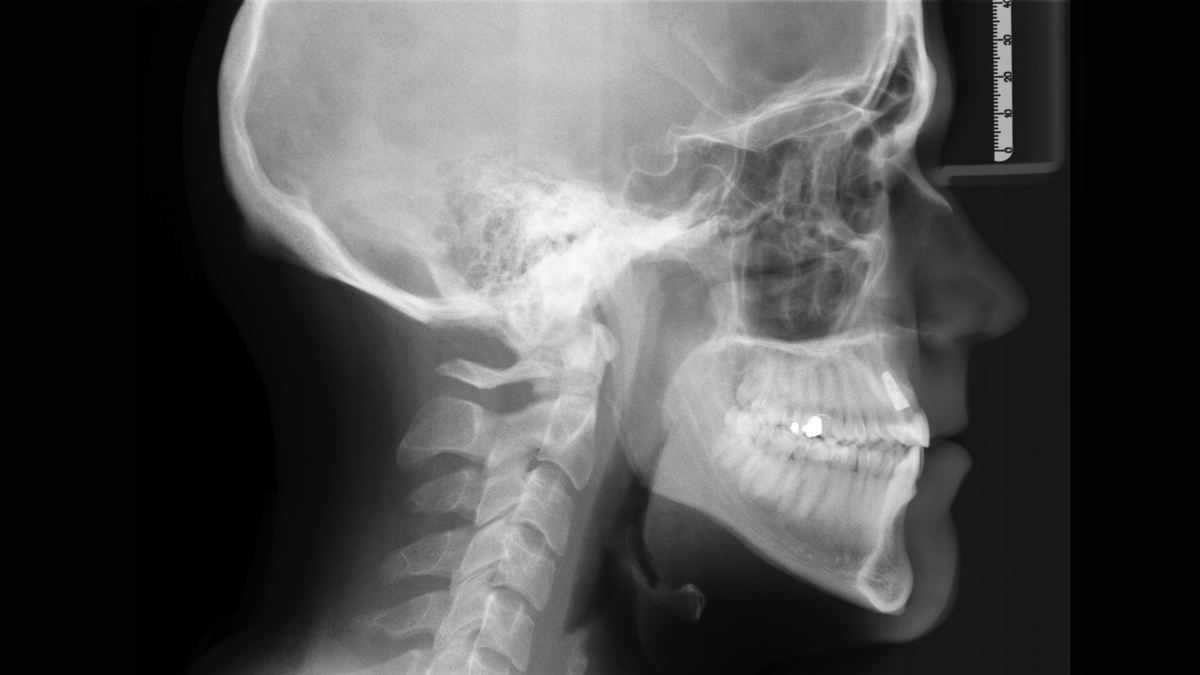

Sample Gallery of Cephalometric Images